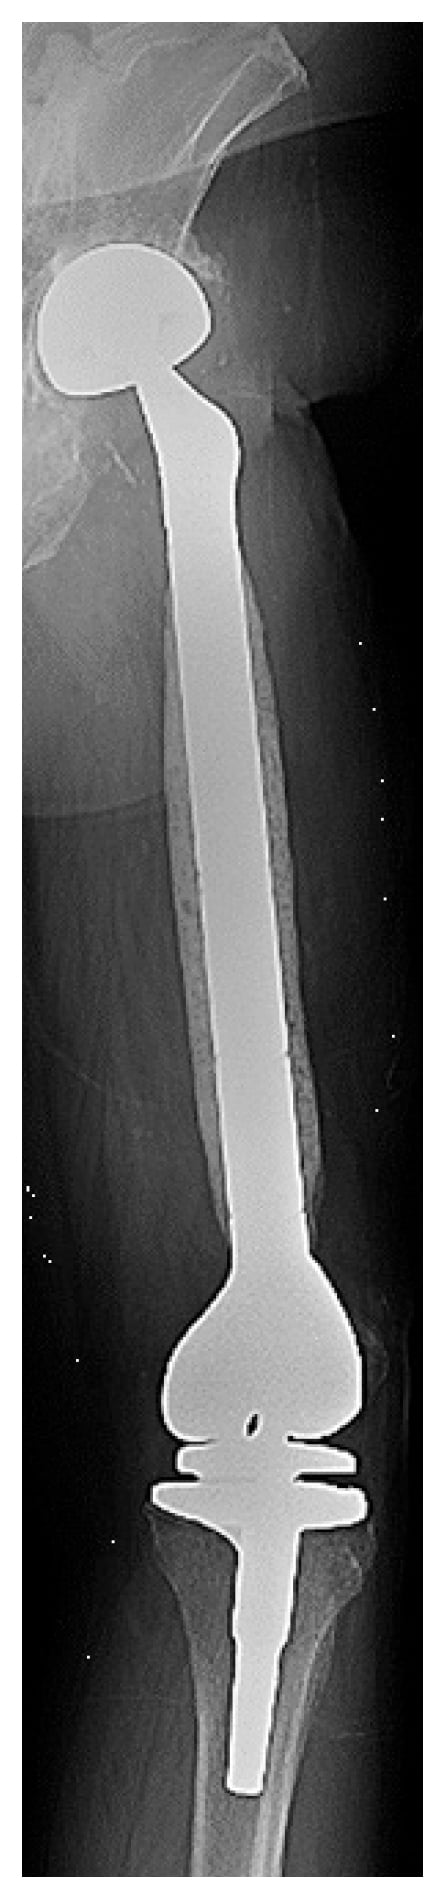

The patient underwent robotic-assisted conversion from a bipolar hemiarthroplasty to THA involving a revision acetabular component (Stryker Trident 2) (Fig. 4). Robotic assistance was deemed necessary due to posterior and medial wall bone loss. Intraoperative cultures were negative. Postoperative pain was substantially reduced, and he was discharged home after 5 days. At 6 weeks postoperatively he sustained a posterior dislocation that was reduced in an emergency room. At 1-year follow-up, the patient used a crutch to mobilize, had a ¾-in. shoe lift, perceived no leg length discrepancy, and was off antibiotics and antifungals.

Figure 4

Figure 4: Postoperative radiograph demonstrates the revision acetabular component with secondary screw fixation following robotic-assisted conversion.

This case also highlights the utility of robotic assistance in acetabular revision, although it is not typically feasible due to artifacts on imaging from the acetabular component. However, bipolar hemiarthroplasty makes computed tomography-based bony segmentation possible, so that the robotic arm can be safely oriented.